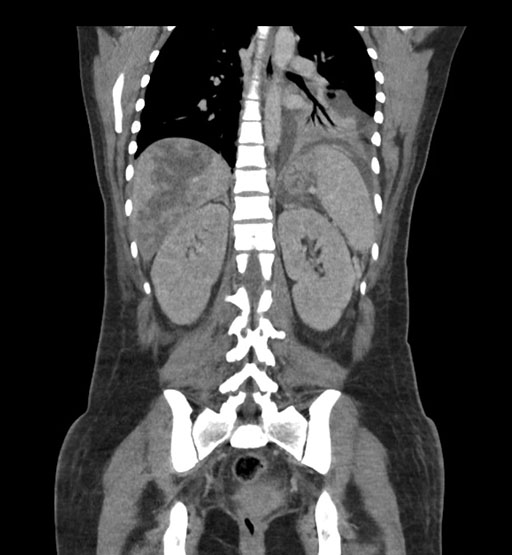

Coronal Arterial